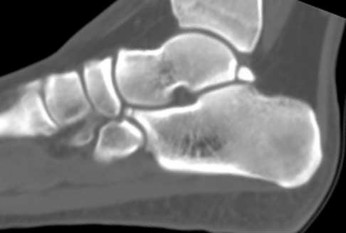

Figures 4a through 4j

1

Normal foot

Figures 4a through 4j do not show any signs of a coalition.